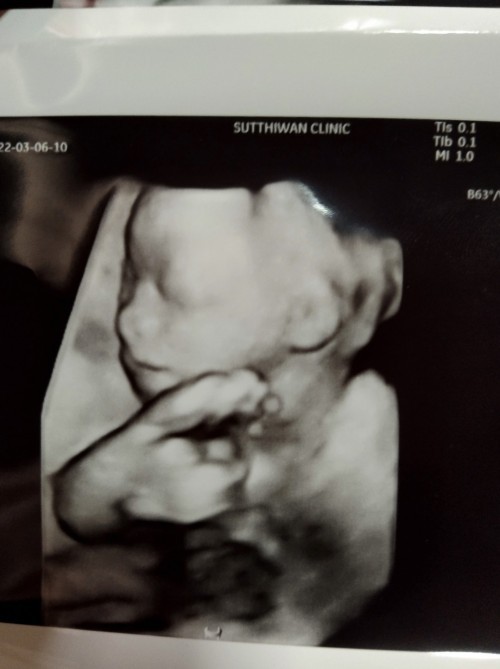

20W หนูเป็นผู้หญิงคะ